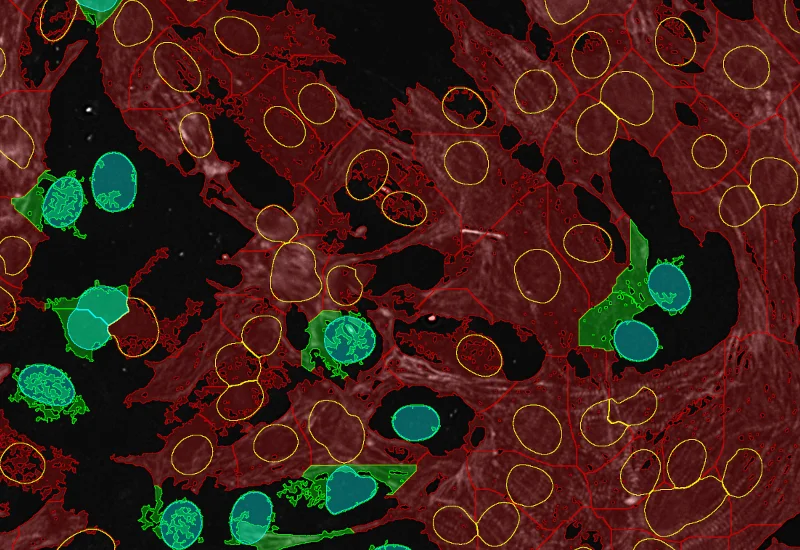

Nuclei detection

Cardiomyocytes (red), fibroblasts (green)